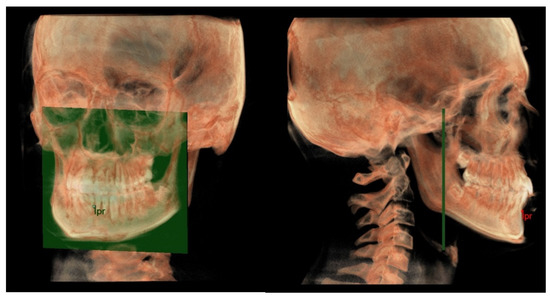

- Maxillary and Mandibular dento-alveolar arches (Figure 2): this parameter compares the lengths of maxillary and mandibular dento-alveolar arches. The maxillary dental arch was measured by the distance between PM and SPr, in parallel with Ref. The mandibular dental arch was measured by the distance between the orthogonal projection of IPr on Ref and Ara, at its intersection point with Ref.

- The mandibular dento-alveolar arch (Figure 9) was measured from the point IPr to a plane passing through the two lingual tuberosity and normal to the axial plane.